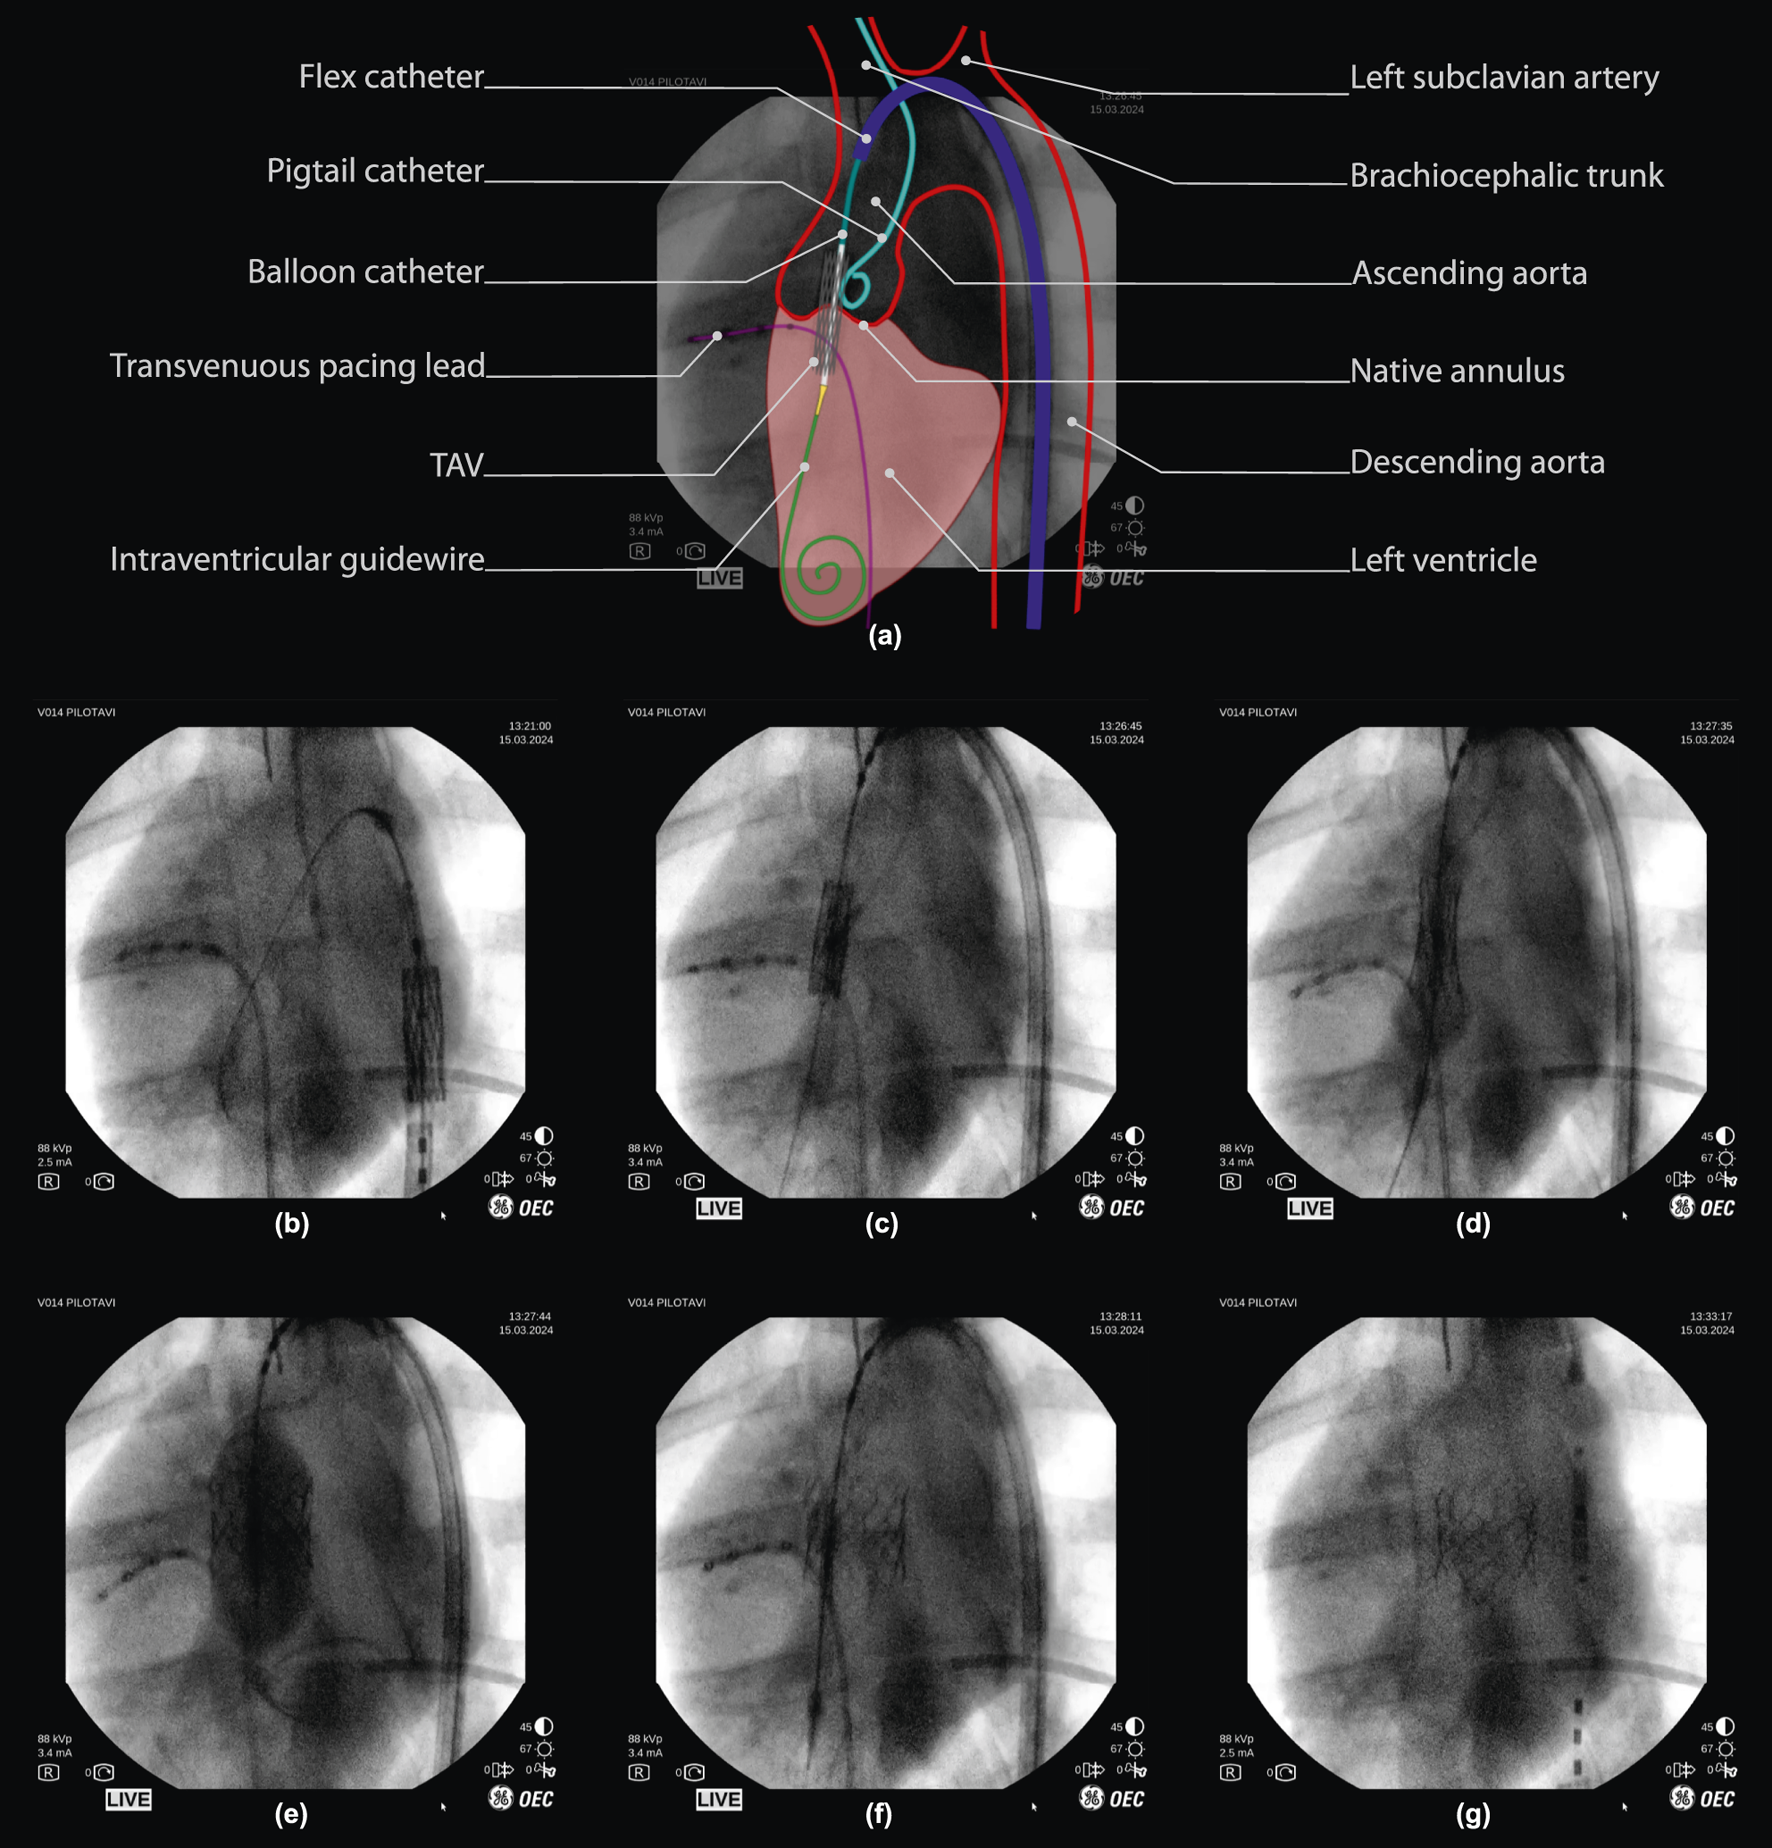

FIGURE 4

Robot-assisted valve implantation sequence on fluoroscopic imaging, with annotated overview. (a) Interpretation of a fluoroscopic image (frame (c), 50% opacity) with an illustrative overlay and annotation of key anatomical features and surgical instruments used during porcine TAV deployment. (below) Fluoroscopy time-sequence: (b,c) Tele-operative positioning of the TAV throughout the aortic arch, into the native valve. (d,e) final TAV positioning and deployment via balloon inflation. (f) balloon deflation, with visual confirmation of initial TAV implantation. (g) Tele-operative instrument retraction, with visual confirmation of TAV implantation. *Note that fluoroscopy frames are unprocessed and included as viewed on the operator monitor of the imaging device (OEC One mobile C-Arm, GE Healthcare, Chicago, IL U.S.A.), including timestamps and other on-screen imaging parameters.

Once in position, the operator tele-operatively deploys the valve implant (Figure 4c). The inflation driver actuates the inflation device at a fixed flowrate (approx. 5mL/sec) to inflate the nominal volume as planned for the chosen TAV (S2). This, while remaining below a pre-determined safe pressure limit (4 bar) using an in-line pressure sensor. The operator retains full control over the inflation via a dead-man switch and is able to pause and continue inflation at will (Figure 4c). Valve deployment is obtained at either full injection of the planned balloon volume or after reaching a pre-defined pressure limit (Figure 4d). Once deployed, the inflation device is used to perform a rapid retraction of the plunger to full retraction, in order to deflate the balloon (Figure 4e). Throughout deployment, the operator remains in full control of all instrument motions to perform any adjustments if required.

Following deployment and balloon deflation, the operator tele-operatively retracts the instruments from the valve region. Stable TAV implant deployment was validated visually on fluoroscopy by an expert TAVI operator directly following deployment, and confirmed once more 5 min after (Figure 4f).

Once valve function is confirmed, instruments are undocked and removed manually from the femoral access region. The procedure is then finalized with access site closure steps as conventional for a three-point access transfemoral TAVI procedure. The overall positioning and deployment sequence was performed in under 1 minute. This is on par with TAVI performed by two operators as per commonplace procedure.